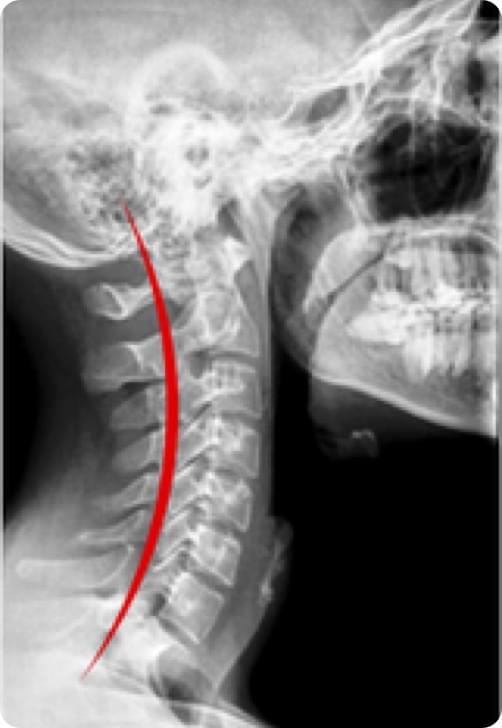

曲度基本恢复正常